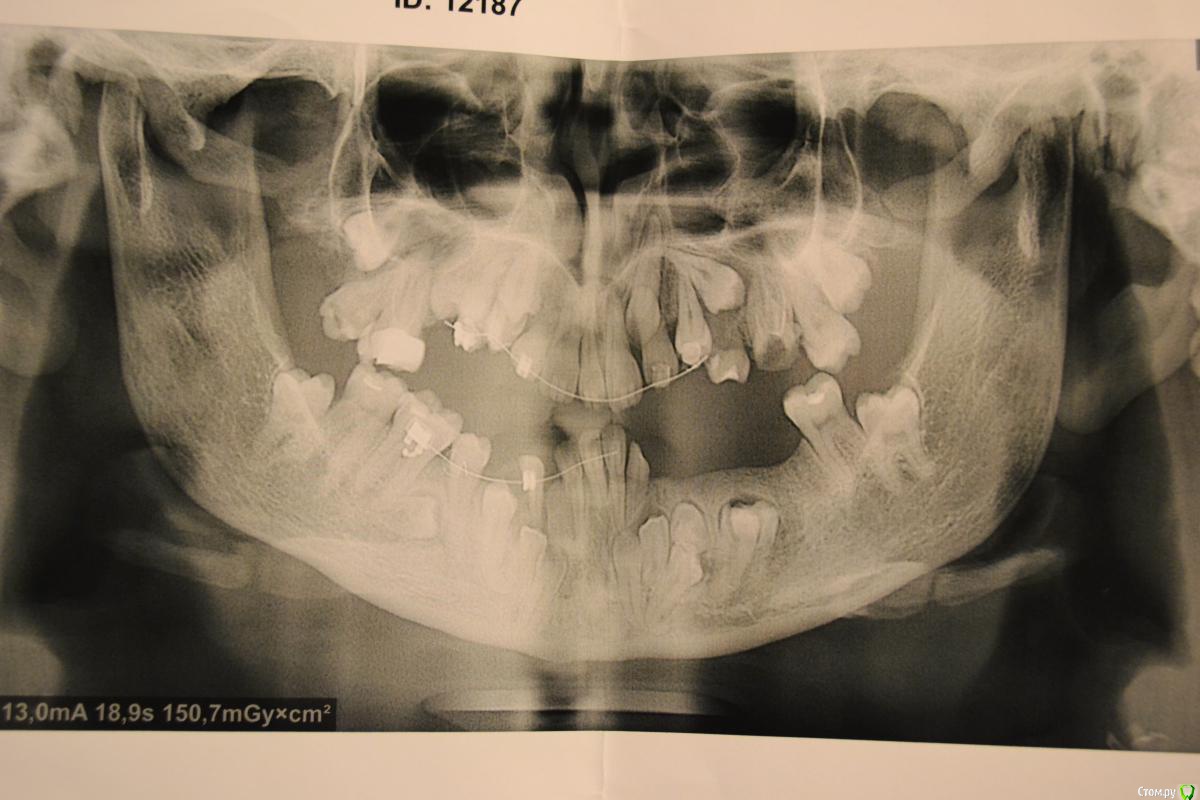

nikor117 Опубликовано 14 октября, 2015 Поделиться Опубликовано 14 октября, 2015 Здравствуйте, уважаемые коллеги.Извиняюсь за качество фото. Хотелось бы помочь пациентке 28 лет. В общем ситуация видна по фото. Сам я ортопед опыта в таких ситуациях нет, возможно подскажете куда ей стоит обратиться. Заранее спасибо. Если нужна дополнительная информация скажите постараюсь выложить. Ссылка на комментарий

nikor117 Опубликовано 14 октября, 2015 Автор Поделиться Опубликовано 14 октября, 2015 Возможность красиво улыбаться, с ее слов на ортодонтии она уже порядка 8 лет, брекеты стоят 1.5 или 2 года, сама врач, сложность ситуации представляет, хочет услышать совет Ссылка на комментарий

Yana guapa Опубликовано 14 октября, 2015 Поделиться Опубликовано 14 октября, 2015 эти фото были ведь на соседнем форуме "...." . там были советы, и хирурги и ортодонты отписывались. причем не так давно. и фото были без брекетов, до начала лечения (около 6 месяцев назад). не похоже на 1.5 года с брекетами здесь . тем, что у нее на зубах стоит сейчас - не помочь это точно. 4 Ссылка на комментарий

Monkey Опубликовано 18 октября, 2015 Поделиться Опубликовано 18 октября, 2015 (изменено) и мне, пожалуйста у пациентки похоже синдром Крузона Изменено 18 октября, 2015 пользователем Monkey 1 Ссылка на комментарий